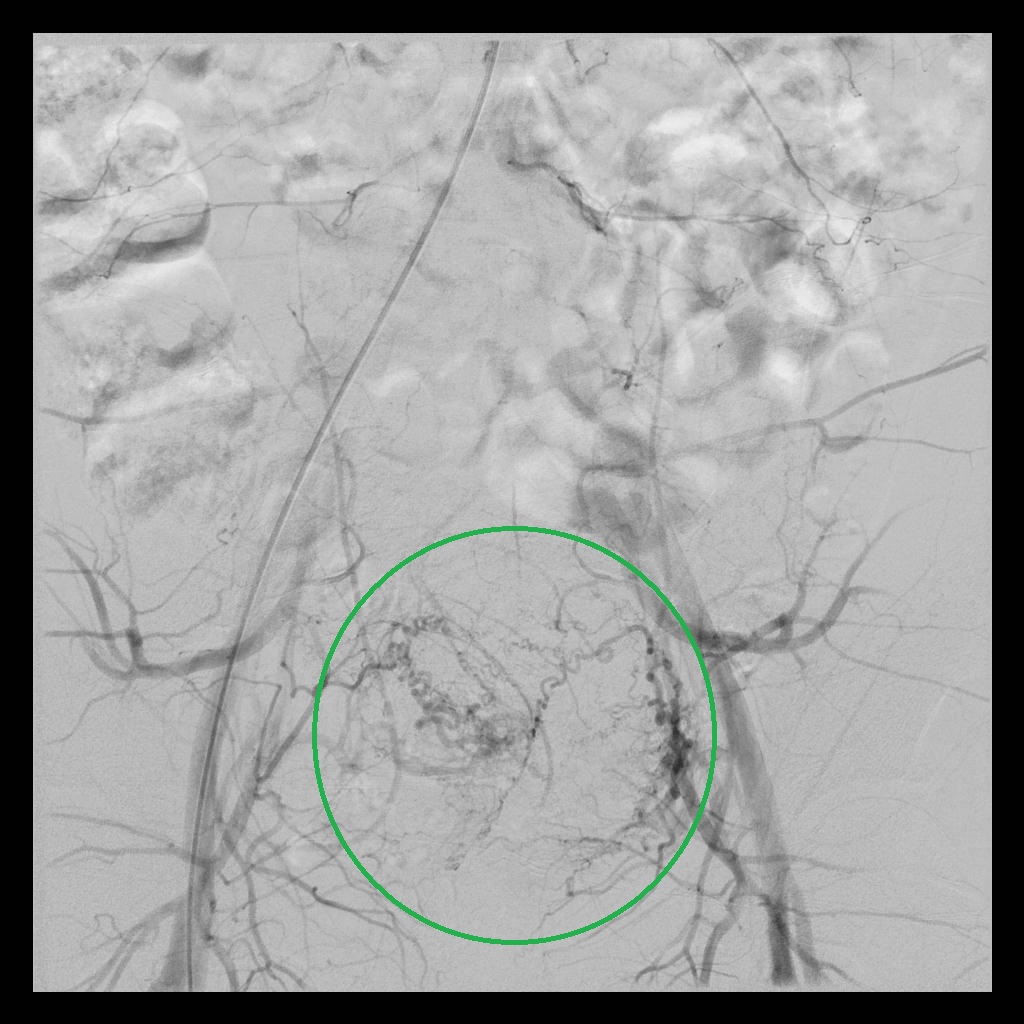

后经腹部主动脉造影显示,子宫双侧的子宫动脉均有增粗、迂曲的情况(下图中红色箭头所示),子宫和子宫肌瘤也均有所增大(下图中绿圈所示)